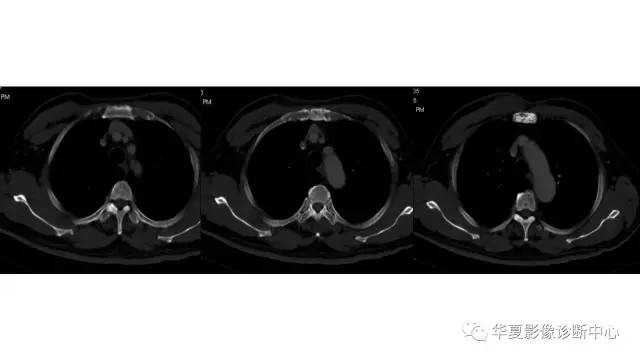

胸壁软骨肉瘤1例CT影像表现